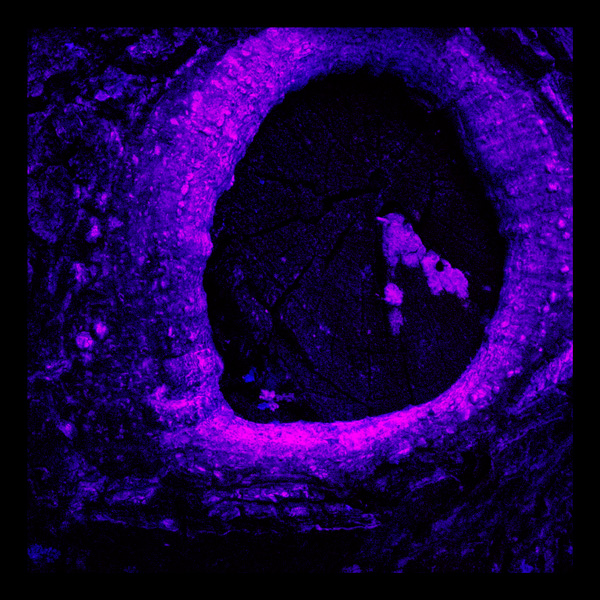

PHOTOGRAPHY